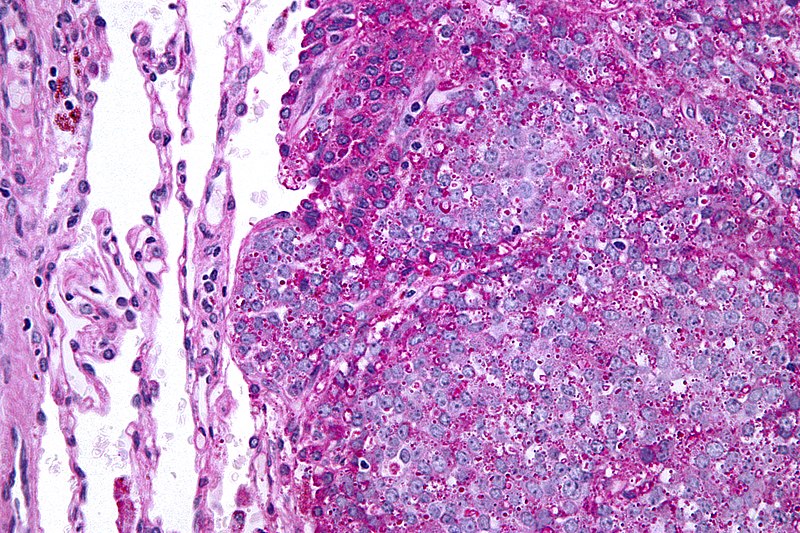

Chondrosarcoma

Chondrosarcoma is a malignant cartilage-forming tumor.

Chondrosarcomas tend to develop in the axial skeleton or pelvic medulla.

Diagnosis of chondrosarcoma is made by biopsy, which shows malignant chondrocytes.